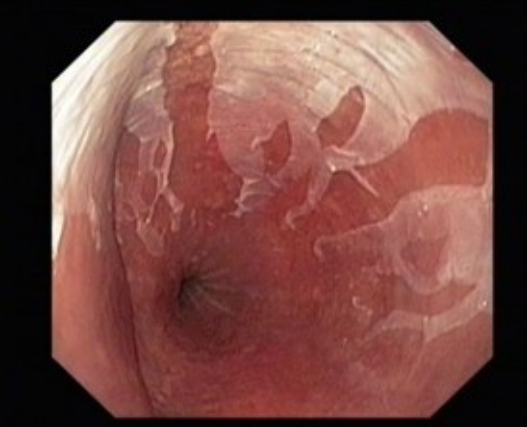

内镜下的典型表现是黏膜脱落。

EGD显示,食管内壁可见易剥离的白色纵向组织贯穿整个食管,止于食管胃交界处,其下层黏膜充血和红斑(图1和图2)。